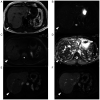

Intrahepatic splenosis (IHS) is a rare disease that is considered to result from heterotopic autotransplantation or implantation of splenic tissue after splenic trauma or surgery. A 46-year-old man with a treatment history of a left lateral liver segmentectomy and splenectomy for a road traffic injury 30 years earlier presented to Sakai City Medical Center (Sakai, Japan) with acute abdominal pain in November 2019. Physical examination showed no significant signs, and serum data were normal. Computed tomography revealed a hypodense mass measuring 2.5x1.7 cm in segment 7 of the liver. Gadoxetic acid-enhanced magnetic resonance imaging showed early enhancement in the arterial phase and washout in the delayed phase. Therefore, laparoscopic surgery was performed with a preoperative diagnosis of hepatocellular carcinoma. Pathological examination of the tumor showed IHS. The postoperative course was uneventful, and the patient developed no new abnormal region in the liver during 2 years of follow-up. The present study presented a case of IHS assumed to be hepatocellular carcinoma. IHS should be considered as a differential diagnosis of a liver mass detected years after splenic trauma or surgery, even in cases with imaging patterns suggesting malignancy.